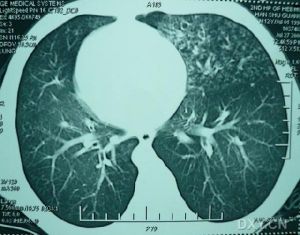

末梢血白細胞總數可升高。胸部X線檢查可見肺紋理增多,心臟轉位;支氣管造影可顯示支氣管擴張,多見於兩肺下葉。診斷

對支氣管擴張伴內臟轉位的患者要考慮Kartagener的可能性。影像學檢查是臨床診斷Kartagener綜合徵的重要依據。胸部X線片、CT掃描、超聲檢查均可發現內臟轉位。治療